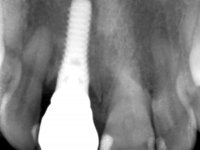

52-year-old female patient, non-smoker. He used an appointment with an implant already placed in the 1.1 site. It was provisionally rehabilitated with a composite resin crown adhered to the palatal surface of the adjacent teeth. This provisional had taken off several times in the last month, even in this first consultation it was taken off. We took advantage of this situation and verified that the “Tissue Level” implant had 2 to 3 mm of prosthetic space available. A deep bite and the inclination of the long axis of the implant posed a very difficult situation for the rehabilitator. If one chooses a abutment with a cemented crown, the height of the abutment would be minimal, with no retention or resistance. If a screwed solution is chosen, the screw access hole would emerge through the vestibular surface. It should be remembered that in 2006 the prosthetic solutions for this situation were limited to these options: 1- Screw-retained angled metal abutment for cemented crown 2 - Screw-retained angled metal abutment for transversally screw-retained crown 3 – Syn Octa metal abutment for screw-retained crown. A serious problem in this rehabilitation was guessed right from the start. The patient had a thick gingival phenotype and good oral hygiene.

After the impression of the implant using a double-mix technique with double viscosity and the collection of shape and color information by the ceramist, we proceed with the work. In the model, a syn octa was placed over the implant, and a screw was placed on it to assess its emergence in relation to the incisal edge. Then, an adequate emergence profile in the artificial gingiva was prepared. A abutment with characteristics suitable for overbite and simultaneously capable of receiving a veneer was waxed on top of this scenario. This waxing gave rise to the manual milling of a very personalized abutment. An infrastructure in Zr was also made for the veneer with a very great adaptation to the abutment. On this infrastructure ceramics were placed. Ceramic fluorescence sought to compensate for the lack of fluorescence that Zr had and obviously further customize the aesthetics. The adhesive bridge was removed and the definitive work was placed. The syn octa was initially tightened with 35 N to the implant and then the Zr abutment was tightened over the syn octa with 15 N. The access hole was plugged and then the veneer was cemented with resin-reinforced glass ionomer. After 15 years, the patient returned to the consultation with tooth mobility. Fortunately, nowadays we have the possibility of having dynamic tightening wrenches that allow tightening screws with greater inclinations. An access cavity was made without damaging the incisal edge of the veneer. Tightening was done with a dynamic wrench with 15 N torque. The hole was covered with Teflon and filled with composite resin. This solution allowed the problem to be solved in a simple and economical way.